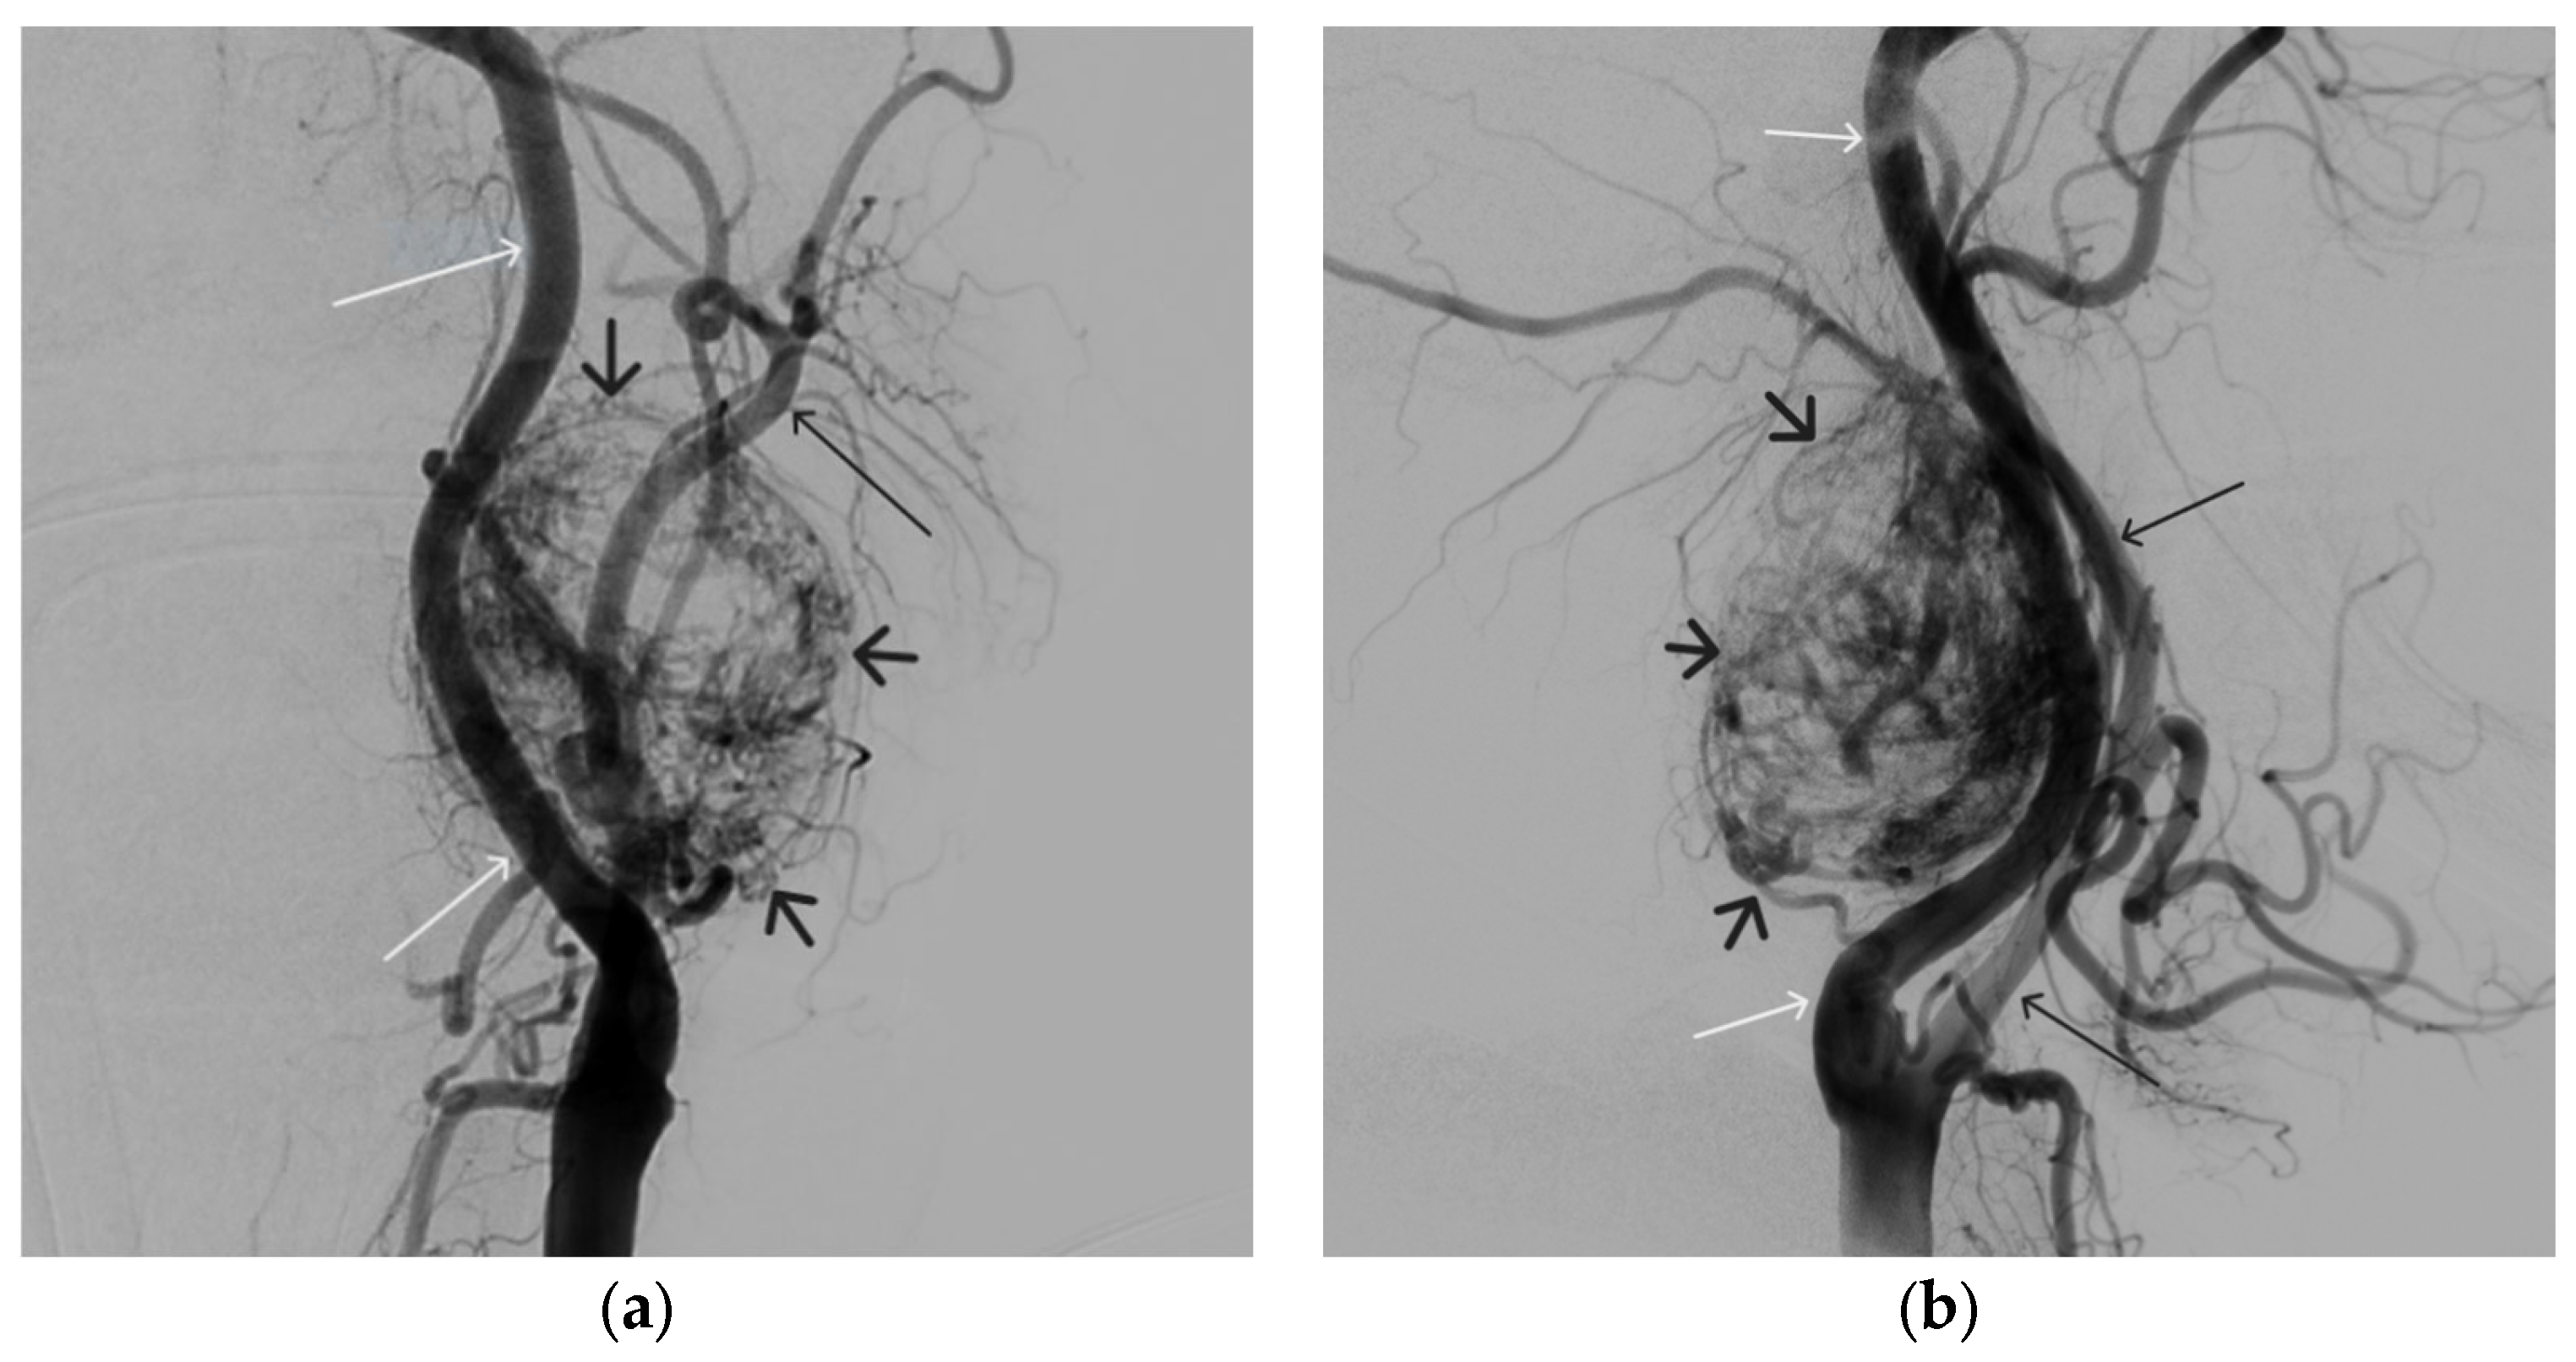

A 48-year-old male patient was admitted to the clinic with complaints of a subcutaneous volume formation in the lower jaw area on the left. Earlier, in another clinic, an attempt was made to embolize the AVM using microcoils. Angiography was performed; filling of the AVM of the soft tissues of the face in the area of the angle of the lower jaw on the left was noted. The presence of separable coils in the afferent from the previous operation was noted; however, the AVM was filled through the coils (Figure 8 and Figure 9). Total embolization of the AVM of the face soft tissues with 7.5 mL of non-adhesive composition ONYX18 was performed. Arteriovenous malformation was totally shut down (Figure 10). There were no complications. The mRs score at discharge was 0.

Figure 8. Digital subtraction angiography from the left external carotid artery, direct projection (white arrow indicates catheter in the left external carotid artery, black arrows indicate contrast AVM).

Gels 09 00954 g008

Figure 9. X-ray, direct projection (the white arrow indicates a microcatheter in the left external carotid artery, the black arrows indicate a complex of microcoils from the previous stage of embolization).

Gels 09 00954 g009

Figure 10. Digital subtraction angiography from the left external carotid artery, direct projection (white arrow indicates the left external carotid artery, black arrows indicate the boundaries of the filled AVM).

Gels 09 00954 g010